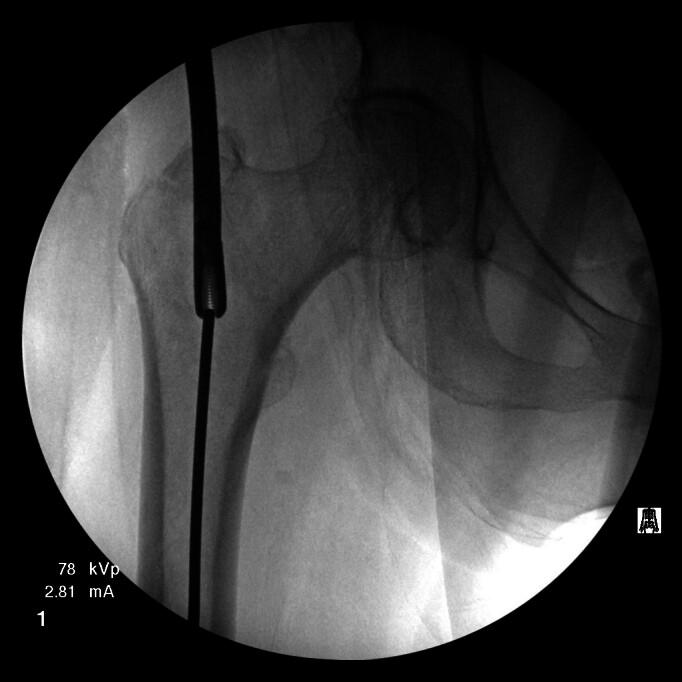

Intramedullary nails are currently the most commonly used device for the fixation of intertrochanteric hip fractures. An initial threaded guidewire is used for localizing the site of entry and determining the final position of the fixation device. Hardware failure with guidewire breakage can complicate the procedure and lead to unplanned challenges for the surgeon. Predisposing mechanical properties of the hardware, along with technical surgical errors may lead to inadvertent breakage or migration of guidewires. The authors report a case of initial threaded starting guidewire migration into the femoral intramedullary canal with subsequent impaction into the distal femoral subchondral bone after advancement of the proximal femoral canal reamer. A method for antegrade removal of a lodged intramedullary guidewire through the distal femoral condyles is described. A set of key technical points to avoid this complication are also provided. Although guidewire migration during hip fracture surgery is a rare occurrence, it is important to recognize the technical measures that can be used to prevent this potentially devastating complication. Surgeons should be familiar with several different techniques for extraction of such hardware surrounding the hip, as there is no universally successful method.